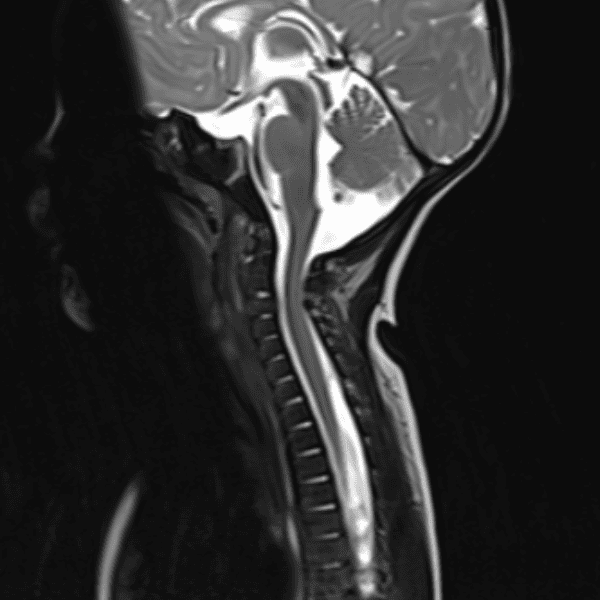

Simulates call by including subtle or difficult cases and some normals.

35 cases